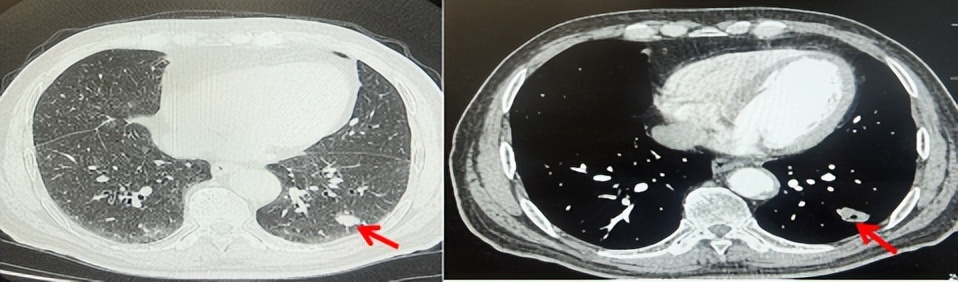

2024.11.19患者出现右侧胸痛,复查胸部CT检查示右侧胸膜肿物,大小约31mmX24mm,右侧4、5肋骨骨质破坏,考虑转移(如图2)。建议患者穿刺活检取病理明确诊断,患者拒绝,经MDT会诊后结合影像学表现及病史考虑为胸膜转移,肋骨转移,分期为rT0N0M1a IVA期,DFS仅仅17个月。2024.12.05起行信迪利单抗联合培美曲塞+卡铂方案治疗4周期,复查胸CT评效PR(如图3)。之后给予信迪利单抗+培美曲塞维持治疗6周期,期间复查CT评效PR(如图3)。目前信迪利单抗+培美曲塞维持治疗中,截止至目前PFS约为8个月,治疗期间未出现明显毒副反应。

图2:患者胸膜及肋骨转移(2024.11)胸部CT肺窗、纵隔窗及骨窗

图3:患者免疫联合化疗治疗后胸部CT,(A、B)图展示信迪利单抗联合培美曲塞+卡铂治疗

4周期(2025.02)疗效,(C、D)图展示信迪利单抗+培美曲塞维持治疗6周期(2025.07)疗效